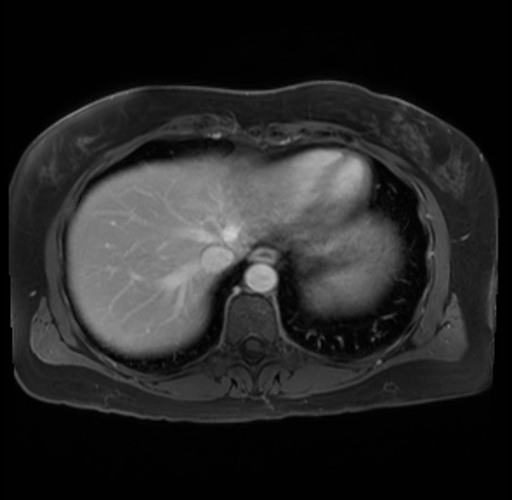

Imaging Analysis

Look through the patient's CT scan to identify any areas of concern for the necessary procedure.

Based on your CT findings, which issue(s) are present and would give reason for "planned slowing down moment(s)" in this case?

Considering a standard distal pancreatectomy procedure, what step(s) of the operation would you do differently in this case?